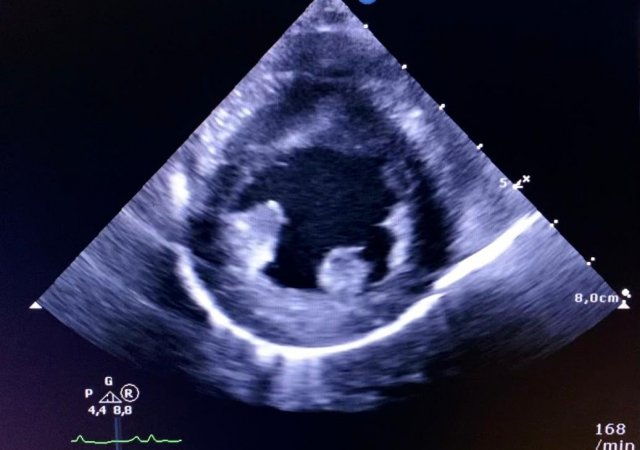

Echokardiographie

Durch ein speziell auf Kardiologie ausgerichtetes „high end“ Ultraschallgerät lassen sich u.a. Herzklappen untersuchen, die Flussgeschwindigkeit des Bluts bestimmen und Turbulenzen des Blutstroms im Herzen erkennen.